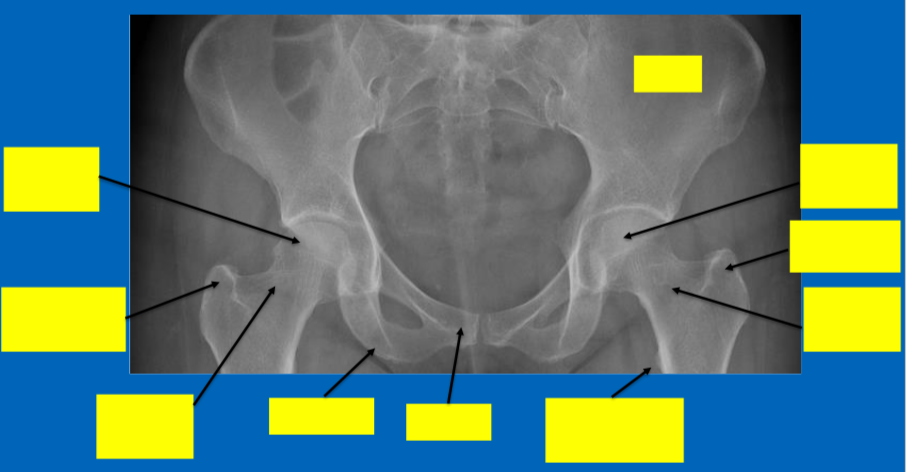

What 3 bones comprise the hip and where are these fused?

Ilium, ischium and pubis → fused at the acetabulum

Identify the blood supply to the femoral head